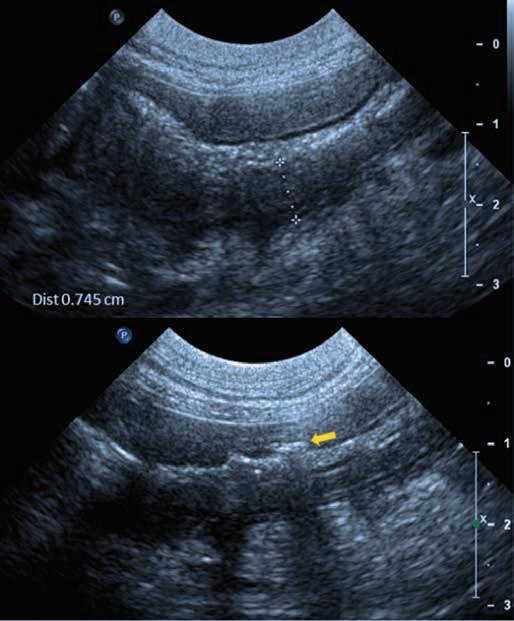

A 3-year-old, male neutered Labrador Retriever presented for chronic diarrhoea. t he patient had a history of inflammatory bowel disease and had undergone multiple previous surgeries for foreign body removal. A colopexy had also been previously performed. t he patient had completed a course of metronidazole on the day of presentation and was also receiving vitamin B12, psyllium husk (metamucil) and probiotics. He was up to date with de-worming treatment and core vaccinations. A three-view abdominal radiograph series was taken as part of the diagnostic workup, and two cropped projections are provided below (Figure 1).

Figure 1. l eft lateral (a) and ventrodorsal (b) abdonimal radiographics of a dog with chronic diarrhoea.

a b